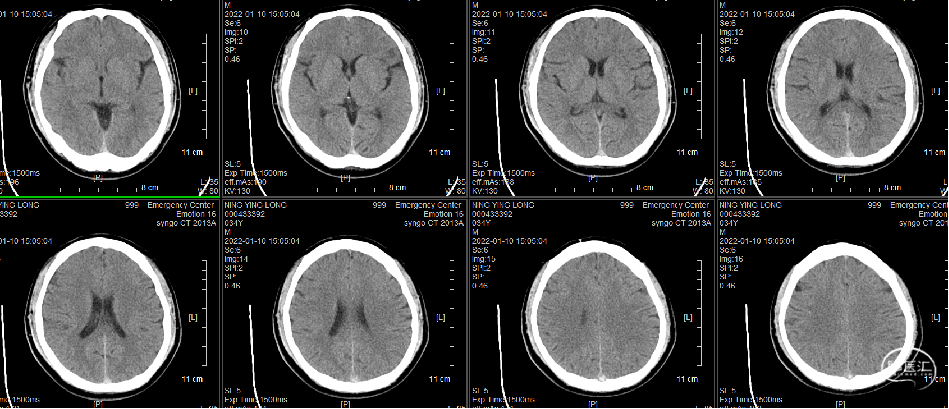

头颅CT(2022-1-10)

脑静脉窦血栓(上矢状窦、右侧横窦、乙状窦)